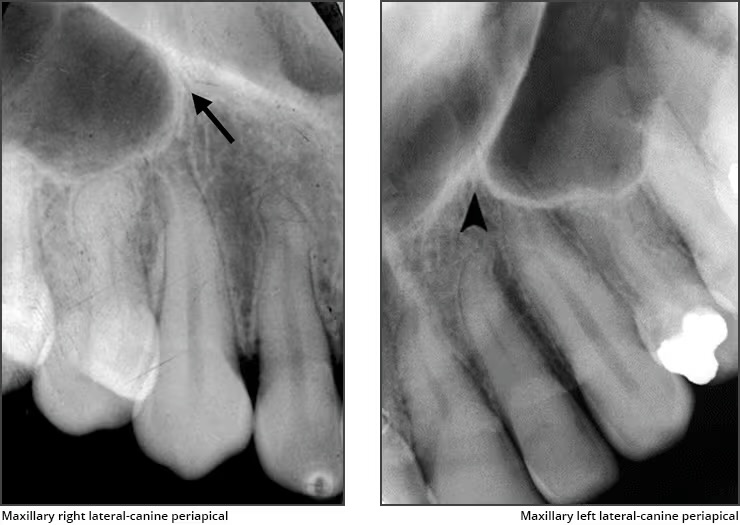

Lateral fossa / canine fossa

Appears bilaterally

Is a slight dip or depression in the bone on the labial of the maxilla near the lateral roots

Recorded don lateral and canine PA’s